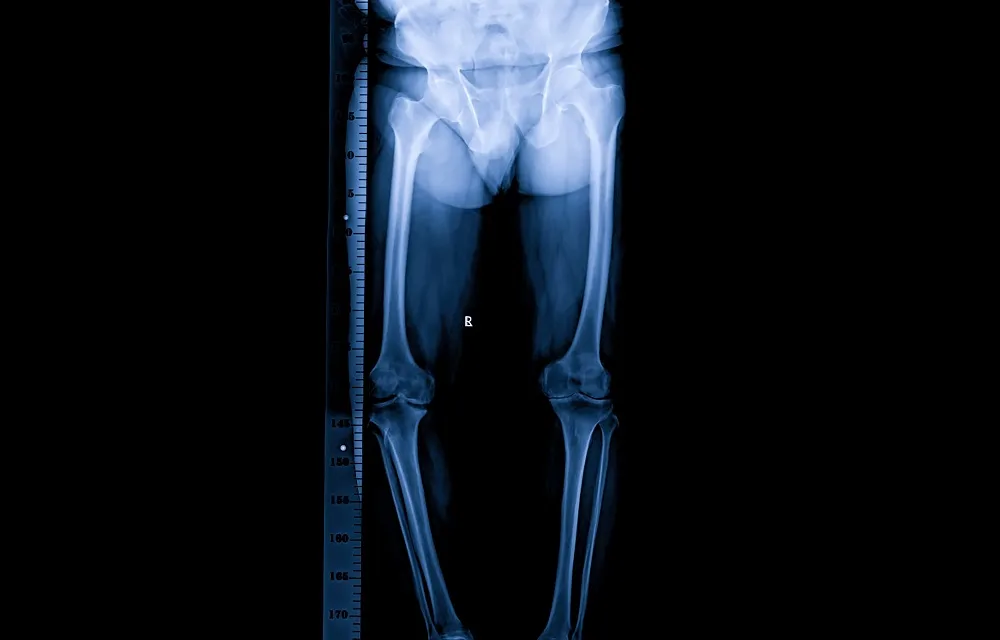

While clinical measurements provide useful estimates, imaging confirms the diagnosis and determines whether the discrepancy is structural or functional. The scanogram X-ray is considered the gold standard for measuring structural leg length discrepancy. This specialized X-ray captures the hips, knees, and ankles in one image with a ruler superimposed directly on the film, allowing precise bone measurements with minimal error (typically within 1-2mm accuracy).

Orthoroentgenograms use three separate X-rays (one each of hips, knees, and ankles) with a ruler included in each image, allowing segment-by-segment bone measurement. EOS imaging, available in select facilities, uses low-dose radiation to create full-body standing images from front and side views, providing excellent visualization of overall alignment and bone length with reduced radiation exposure.

CT scanograms offer extremely precise measurements through cross-sectional imaging and are particularly useful when deformities make it difficult to interpret standard X-rays. For children still growing, an X-ray of the hand and wrist determines bone age (skeletal maturity), helping predict remaining growth and future discrepancy at skeletal maturity—essential information for surgical planning.